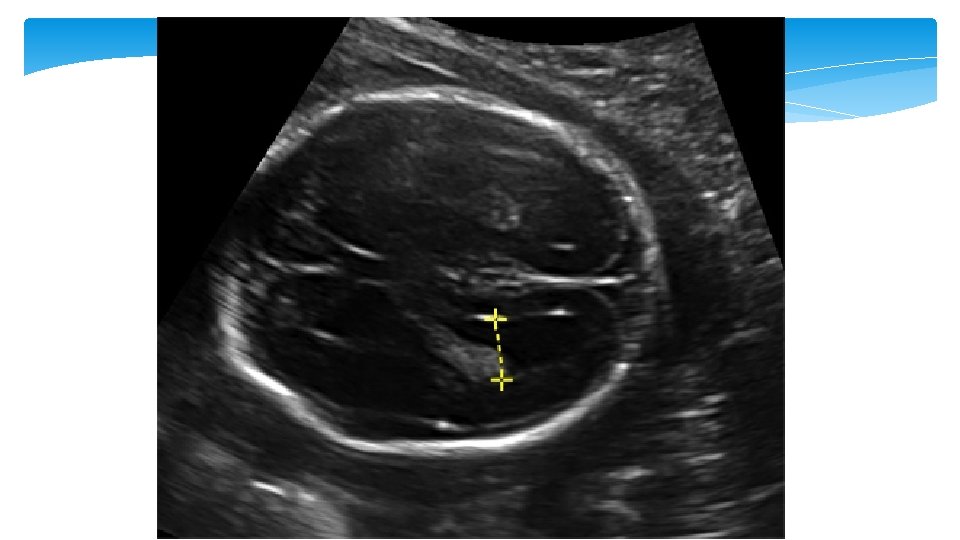

Mild ventriculomegaly Ventriculomegaly is a condition caused when there is dilated atrium beyond 10 mm. The mild ventriculomegaly (MVM), or what is called borderline ventriculomegaly, range between 10 – 12 mm and 10– 15 mm. It can be an isolated finding or be associated with an underlying cranial defect or anomaly such as agenesis of the corpus callosum

Ventriculomegaly Isolated ventriculomegaly is a risk factor for Down syndrome Mild ventriculomegaly is detected in 4 to 13 percent of fetuses with Down syndrome and 0. 1 to 0. 4 percent of euploid fetuses The risk of abnormal outcome, such as Down syndrome, increases with the degree of ventriculomegaly, progression of ventriculomegaly, and presence of other anomalies.

Soft marker Second trimester: echogenic bowel Second trimester: thickened nuchal fold Second trimester: mild ventriculomegaly Imaging criteria Aneuploidy association Management Fetal small bowel as echogenic as bone • LR 5. 5 to 6. 7 for Down syndrome • Associated with aneuploidy, intraamniotic bleeding, CF, CMV 1. Further counseling 2. Offer CMV, CF, and aneuploidy screening or diagnostic testing ≥ 6 mm from outer edge of the occipital bone to outer skin in the midline • LR 11 to 18. 6 with 40 to 50% sensitivity and >99% specificity for Down syndrome • Most powerful secondtrimester marker 1. Detailed anatomic survey 2. Further detailed genetic counseling and aneuploidy screening or diagnostic testing • Associated with aneuploidy • LR 25 for Down syndrome 1. Genetic counseling 2. Second-trimester detailed anatomic ultrasound evaluation 3. Consider diagnostic testing for aneuploidy and CMV 4. Repeat ultrasound in third trimester Lateral ventricular atrial measurement between 10 to 15 mm